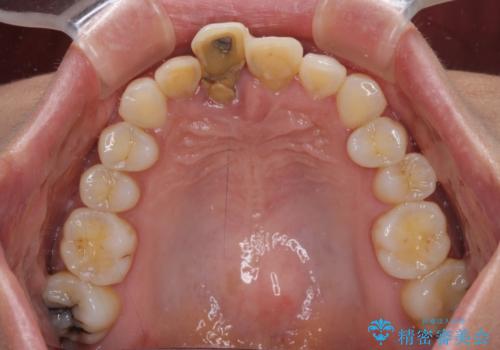

- 仮歯のまま前歯を放置しているとのことで来院された患者様です。

目視で確認できるほどしっかりとした破折が認められ、抜歯が必要と判断されました。

抜歯後は歯肉が痩せてしまうため、歯肉移植を行って歯肉の形態を改善した後、オールセラミックブリッジにて補綴することとしました。